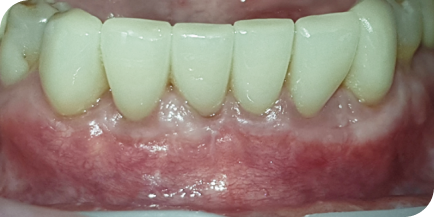

Случай из практики.

Лечение пародонтита

Пациентка (Ольга, 38 лет) обратилась в нашу клинику с жалобами на боль в дёснах, подвижность зубов, неприятный запах изо рта.

Мы провели полную диагностику. Диагноз — хронический генерализованный пародонтит средней степени тяжести. Выявлены проблемы: подвижность зубов 1-й степени, пародонтальные карманы более 5 мм, убыль костной ткани на 1/2 длины корня зуба.

Пародонтит — это воспалительные поражение окружающих тканей зуба, проникающее глубоко под десну. Воспаление вызывает разрушение костной ткани и связок зуба. На исходном фото это хорошо видно.

Провели консервативную пародонтологию и кюретаж зубодесневых карманов без разрезов и без швов.

Через 10 дней провели повторную чистку и полировку.

У пациента болей в десне больше нет, пародонтальные карманы отсутствуют, подвижность зубов отсутствует, убыли костной ткани больше нет, неприятный запах изо рта больше не наблюдается.